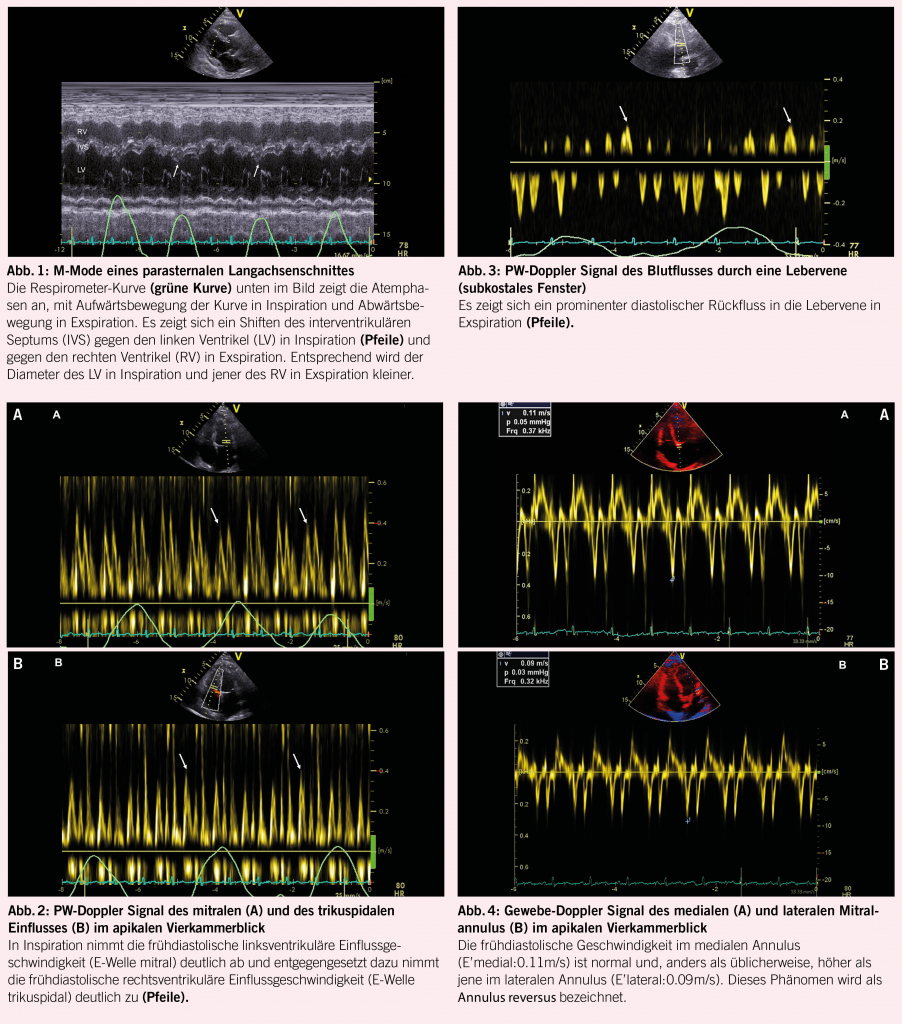

Ein 65-jähriger Patient klagte in den vergangenen Monaten über eine zunehmende Dyspnoe. Diese ging mit einer progredienten Müdigkeit einher. Im Verlauf kam es auch zu zunehmenden Unterschenkelödemen und zu einem Druck im Oberbauch. Im Rahmen der Abklärungen wurde eine transthorakale Echokardiographie durchgeführt. Sowohl die linksventrikuläre, als auch die rechtsventrikuläre systolische Funktion erwiesen sich dabei als normal. Es fiel jedoch eine atemvariable Bewegung des interventrikulären Septums auf, mit einem Shift des Septums gegen den linken Ventrikel in Inspiration und gegen den rechten Ventrikel in Exspiration, was besonders gut im M-Mode des parasternalen Langachsenschnittes dargestellt werden konnte (Abb. 1). Ebenfalls zeigte sich im PW-Doppler eine Atemvariabilität der Einflussmuster durch die AV-Klappen, mit Abnahme der transmitralen E-Welle in Inspiration und Zunahme in Exspiration (Abb. 2A) und entgegengesetztem Verhalten der transtrikuspidalen E-Welle (Abb. 2B). In der PW-Doppler Untersuchung einer Lebervene konnte ein prominentes diastolisches Rückfluss-Signal in Exspiration dargestellt werden (Abb. 3). Im Gewebe-Doppler des medialen und lateralen Mitralklappenannulus zeigten sich erhaltene frühdiastolische Geschwindigkeiten (E’), wobei das me-diale E’ (Abb. 4A) höher war als das laterale E’ (Abb. 4B). Die Doppler-echokardiographisch erhobenen Befunde waren klassisch für das Vorliegen einer Pericarditis constrictiva. Der Patient wurde nach Vervollständigung der Abklärungen einer Perikardektomie unterzogen, was im Verlauf zur deutlichen Reduktion seiner Beschwerden führte.

Die Doppler-Echokardiographie ist in der Lage, diese pathophysiologischen Veränderungen aufzuzeigen. Als nützliche und indikative echokardiographische Parameter erweisen sich bei der Pericarditis constrictiva das respiratorische Shiften des ventrikulären Septums, in Inspiration gegen den linken, in Exspiration gegen den rechten Ventrikel (Abb. 1) (4), die Abnahme der transmitralen E-Welle und die Zunahme der transtrikuspidalen E-Welle in Inspiration (Abb. 2A und B) (4, 5), der exspiratorisch betonte diastolische Rückfluss im PW-Doppler Signal der Lebervenen (Abb. 3) (5), die erhaltene oder akzentuierte frühdiastolische Gewebe-Doppler Geschwindigkeit im medialen Mitralannulus (E’ medial; Abb. 4A) (6) und der sogenannte Annulus reversus, d.h. das Vorliegen eines gleich hohen oder höheren E’ im medialen verglichen zum lateralen Annulus (Abb. 4A und B) (7). Letzteres Phänomen kommt durch das Tethering des lateralen Annulus infolge des konstriktiven perikardialen Prozesses zustande.

Gemäss einer Studie der Mayo-Clinic scheinen der respiratorische Shift des interventrikulären Septums, das erhaltene oder erhöhte mediale E’ und das exspiratorisch betonte diastolische Backflow-Signal in den Lebervenen am engsten mit der Diagnose der Pericarditis constrictiva assoziiert zu sein (3).